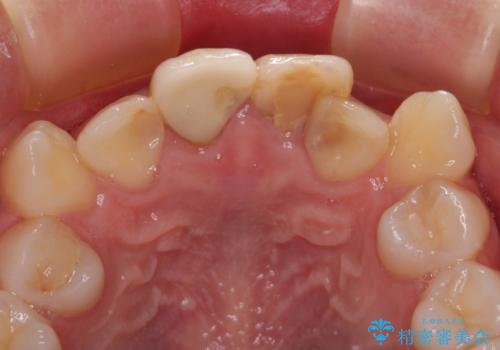

- 学生の頃に神経を取り除いた前歯の変色と、色合いの悪いかぶせ物が気になるとのことで来院された患者様です。

レントゲン写真より、歯根の炎症が認められず、土台もしっかりと植立されていたため、仮歯に置き換えた後にオールセラミッククラウンにて補綴することとしました。